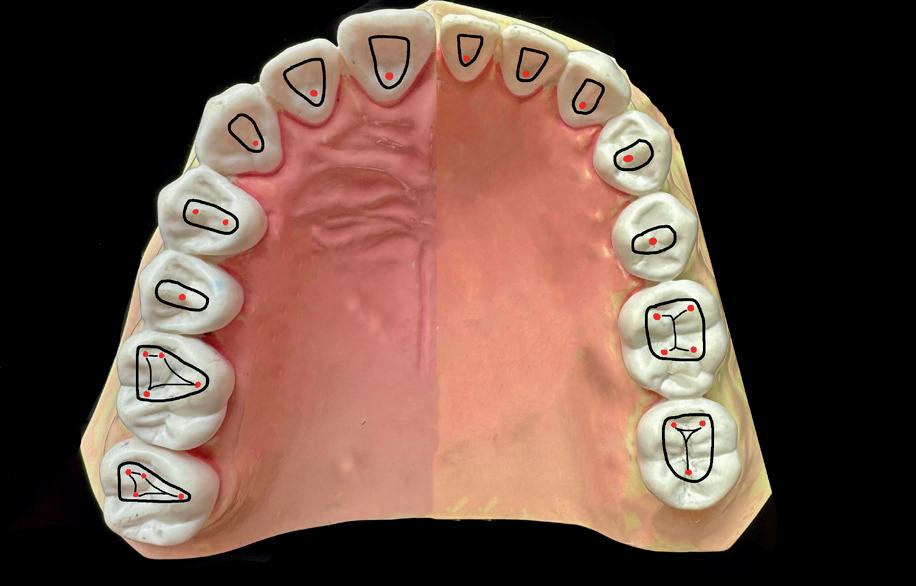

Voordat je aan een wortelkanaalbehandeling begint, zorg je voor (of maak je) een goede beginfoto waar het te behandelen gebitselement volledig op staat afgebeeld. Deze foto geeft essentiële informatie: de grootte van de pulpakamer en de ligging ervan; het aantal en de vorm van de wortels en de breedte van hun wortelkanalen en de lengte van de wortels. Hiermee kan je de DETI-score bepalen en de moeilijkheidsgraad inschatten. De grootte en de ligging van de pulpakamer op de röntgenfoto in combinatie met de ideale anatomische vorm, zoals in foto 1 is aangegeven, bepaalt de uiteindelijke vormgeving van de opening. Bij de molaren liggen de kanaalingangen in de buurt van de knobbeltoppen. Als die niet meer in originele staat

(kroon, restauratie) zijn, kan je ook de wortel gebruiken. Soms moet je net subgingivaal sonderen, maar de kanaalingang ligt in het middel van de wortel. Als je die plek visualiseert en projecteert op je opening, boor je de goede kant op. Nog een tip: wees bij het openen niet spaarzaam met het wegnemen van aanwezig restauratiemateriaal (wees wél spaarzaam met het onnodig wegnemen van tandweefsel).

1. De locatie van de kanaalingangen ten opzichte van de occlusale morfologie (rood). In zwart is de ideale of standaard opening ingetekend. De uiteindelijke vorm van de opening is voorts ook afhankelijk van de klinische situatie, die vooral vanuit een goede begin foto wordt verkregen.